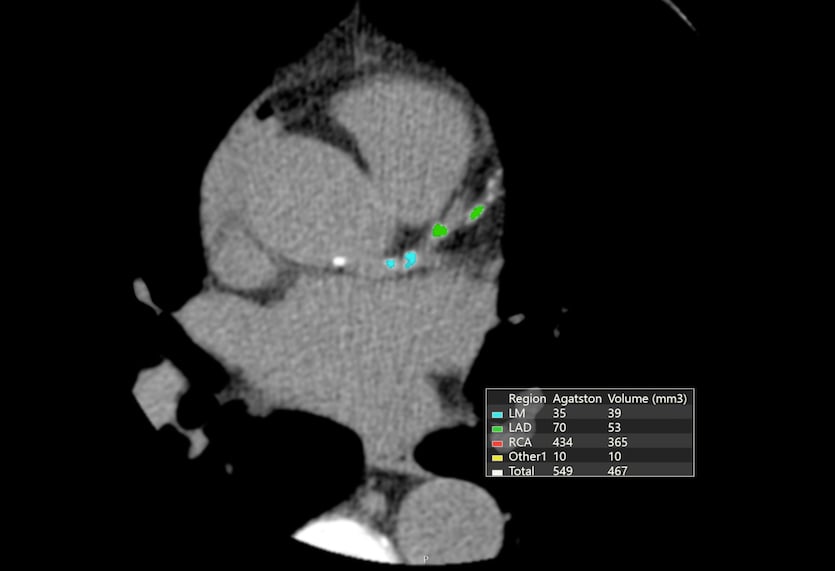

Radiologist In Qatar Cardiac Ct Scan Naseem Al Rabeeh